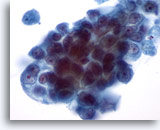

Figure 54

Breast FNA, Medullary carcinoma.

Fine-needle aspirates from these tumors typically show clusters of large pleomorphic tumor cells with prominent nucleoli, admixed with lymphocytes as seen here. Plasma cells may also be seen. 40x

Figure 54

Breast FNA, Medullary carcinoma.

Fine-needle aspirates from these tumors typically show clusters of large pleomorphic tumor cells with prominent nucleoli, admixed with lymphocytes as seen here. Plasma cells may also be seen.

40x